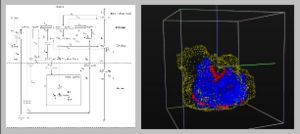

Background/Purpose: Related also to efforts within the Center for the Development of a Virtual Tumor, CViT (http://www.cvit.org), our research here (http://biosystems.mit.edu) focuses on developing multi-scale and multi-resolution (brain) cancer models. Using a hybrid 3D agent-based modeling platform we connect gene-protein interaction maps on the molecular and single cell level (Figure 1, left) up to the volumetric tumor scale of clinical MR-images. For the latter, we plan on using Slicer for segmentation of tumor-affected areas and 3D reconstruction of tumor volume and surface. Amongst the more challenging steps is the translation of these 2D in vivo imaging data onto our in silico lattices. Figure 1 (right) depicts a first step towards this approach where the yellow points depict the 3D surface reconstruction of a T1+Gd MRI while the blue and red points represent virtual tumor cells in attempt to match the real data points.